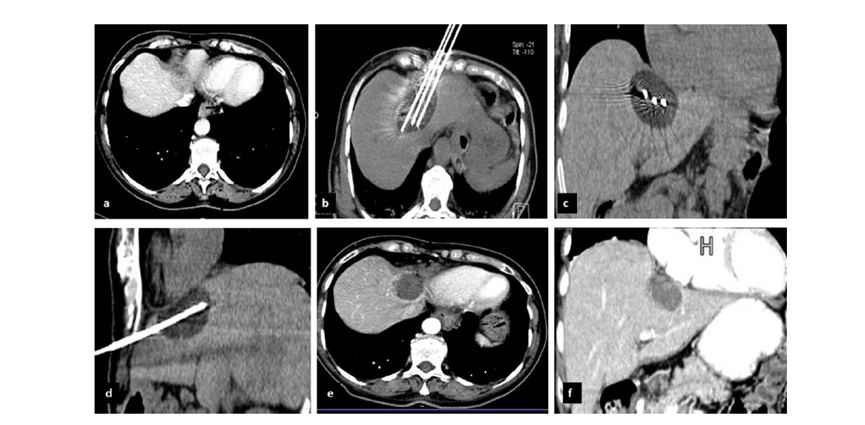

51歲男性患者,肝移植后復(fù)發(fā)病例

(a) 射頻消融后在病變邊緣顯示殘余增強(qiáng)。

(b) 冷凍消融術(shù)中影像顯示冰球完全覆蓋病變。

(c) 19個(gè)月后隨訪,沒有發(fā)生局部腫瘤進(jìn)展。